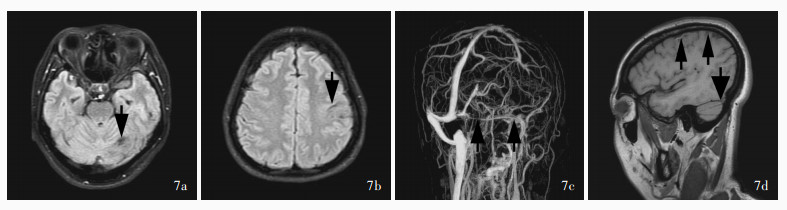

Hu SY , Zhang KY , Gu YQ , Li JK , Zhou C , Ji XM , Duan JG . Exploration of glucocorticoid combined with anticoagulation in acute/subacute severe cerebral venous thrombosis. Shou Du Yi Ke Da Xue Xue Bao, 2023, 44: 280- 288.

胡舒缘, 张开元, 谷亚钦, 李京凯, 周陈, 吉训明, 段建钢. 糖皮质激素联合抗凝在急性/亚急性重症颅内静脉血栓治疗中的探索. 首都医科大学学报, 2023, 44: 280- 288.

Hu S, Gu Y, Zhao T, Zhang K, Li J, Zhou C, Song H, Liu Z, Ji X, Duan J. Steroids combined with anticoagulant in acute/subacute severe cerebral venous thrombosis[J]. Chin Med J (Engl), 2025. [Epub ahead of print]